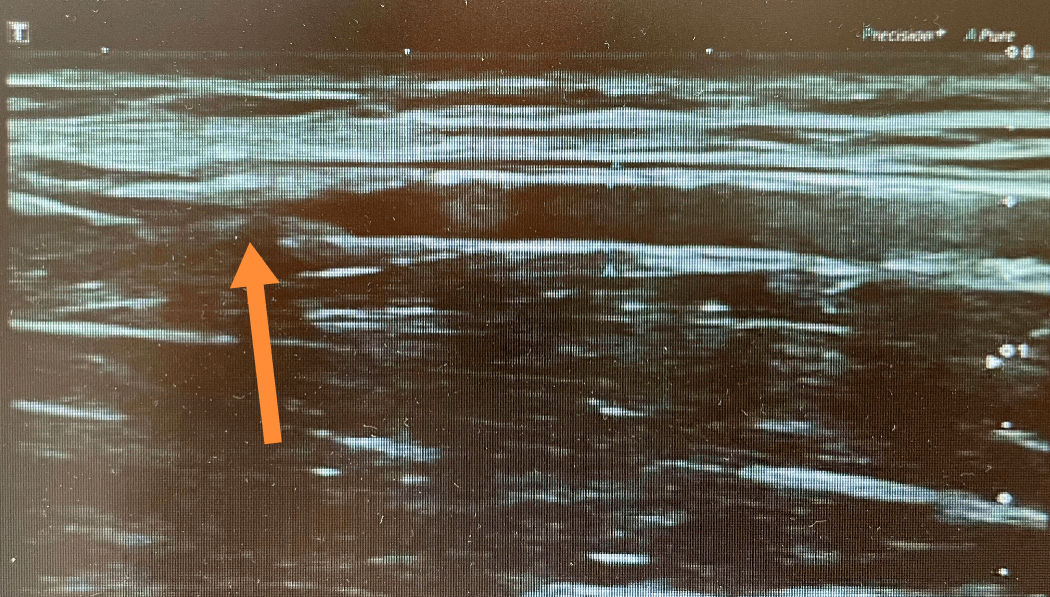

根据何先生复杂的疾病过程 , 入院后张东亮主任医师对患者进行了详细的体格检查 , 并安排了内瘘血管彩超评估、血管CTA等检查 。 结合检查结果 , 张东亮主任医师带领全科大夫就下一步患者血管通路建立方式问题进行了术前讨论及查房 。 如果继续应用右侧中心静脉导管透析 , 导管相关感染、出血、血栓、透析不充分等一系列危害始终存在 , 该方案首先被排除 。 然而右手前臂的血管虽然没有做过血管内瘘手术 , 但血管条件很差(因心内膜炎造成的长达一年余静脉抗生素输液史 , 多年高血压、冠心病、心梗病史 , 血管内膜粥样硬化明显 , 尿毒症高磷动脉中膜钙化严重) , 右侧前臂血管肘部桡动脉内径0.27cm , 多发狭窄斑块 , 最窄处内径0.1cm , 血速明显减低 , 可见侧支循环供血(图4、图5) , 头静脉全程闭塞 , 显然不适合做标准右手腕部动静脉内瘘 , 而超声显示右肘部的血管动脉、静脉的条件可以用于高位内瘘手术 。 手术方案争论的焦点集中在右肘部的肱动脉和肘正中静脉做高位自体动静脉内瘘、还是人工血管动静脉内瘘 。

文章图片

图4 狭窄的桡动脉